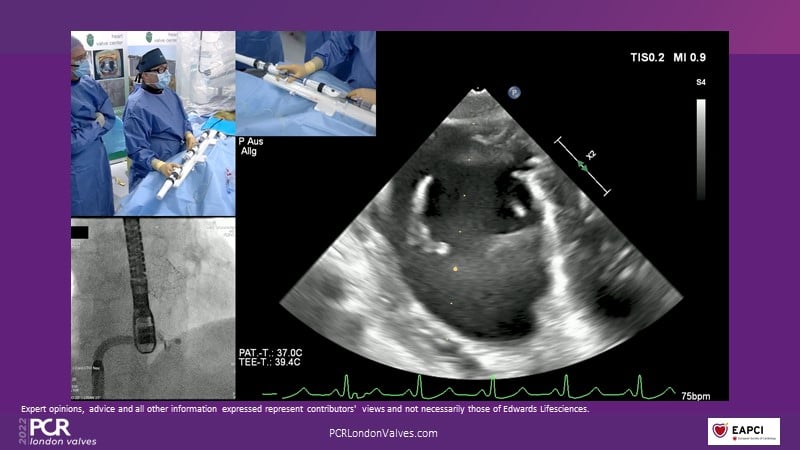

This innovative session takes you through the patient selection and anatomical characteristics when selecting amongst the different transcatheter options to treat tricuspid regurgitation, followed by a recorded demonstration using the PASCAL Precision repair system.

- To participate in a recorded demonstration using the PASCAL Precision repair system for the treatment of tricuspid regurgitation